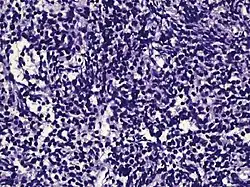

| Small-cell carcinoma | 0.3–2%[14][15][notes 1] |

|

Half of cases have usual acinar components[1] |

||||